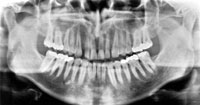

Jednym z najnowocześniejszych jest aparat do wykonywania zdjęć pantomograficznych mający główne zastosowanie w stomatologii. Dawka promieniowania przy zdjęciu pantomograficznym jest porównywalna z dawką promieniowania przy wykonywaniu jednego zdjęcia zębowego. Jeśli chcielibyśmy wykonać zdjęcie wszystkich zębów pojedynczymi zdjęciami zębowymi, pacjent narażony byłby na 12-krotne naświetlanie. Dzięki możliwości wykonania zdjęcia pantomograficznego dawka promieniowania jest 6-8-krotnie mniejsza

Wykonanie zdjęcia pantomograficznego jest dla pacjenta przyjemnym, bezbolesnym i bezpiecznym badaniem. Pacjent siedzi w fotelu, a układ głowica-klisza automatycznie obraca się wokół jego głowy. Ten rodzaj projekcji, ma bardzo duże znaczenie diagnostyczne w całej stomatologii. Na zdjęciu pantomograficznym - poglądowym widoczne są wszystkie zęby, zarówno ich korony jak i korzenie. Ułatwia to bardzo wykrycie próchnicy wczesnej, próchnicy wtórnej pod wypełnieniami, próchnicy korzenia. Istotne jest to, że doskonale widać próchnicę na powierzchniach stycznych zębów, która nie jest dostępna w badaniu klinicznym ani dla oka lekarza, ani dla narzędzi, którymi się on posługuje. Uwidacznia wielkość i lokalizację zmian chorobowych, co pozwala przewidzieć ich przebieg i zaplanować najskuteczniejszy sposób zatrzymania procesu niszczenia kości czyli jest idealnym narzędziem w walce z paradontozą. Zdjęcie pantomograficzne jest nieocenione również w protetyce przy planowaniu uzupełnień protetycznych. Wskazuje, które zęby trzeba koniecznie usunąć, a które wyleczyć zachowawczo lub kanałowo, by mogły spełniać rolę filarów dla przyszłych protez, mostów, koron. Uwidacznia także pozostawione korzenie, które przed podjęciem leczenia protetycznego należy usunąć. Na zdjęciu tym można ocenić ponadto przebieg szczelin złamania żuchwy oraz wstępnie stan zatok szczękowych i stawu skroniowo-żuchwowego. Dlatego w nowoczesnej stomatologii zdjęcie pantomograficzne to najważniejsze badanie dodatkowe, które ułatwia lekarzowi postawienie prawidłowej diagnozy i zaplanowanie leczenia.